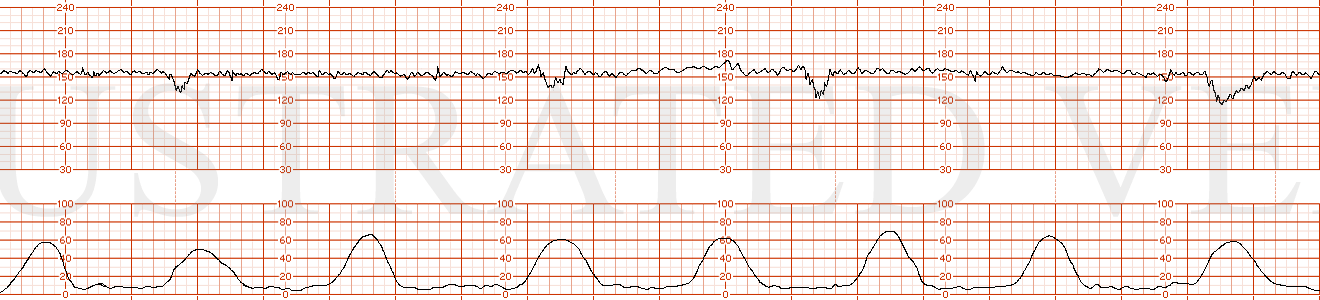

STRIP 71

1. 1st panel:

Contractions – average of 4 contractions / 10 minutes each symmetric x 60 seconds 3rd too long 30secs, 4th too long 20secs,

Baseline 1 – 145 with average variability

Decelerations 1 - none

Accelerations1 – none

2nd panel:

Contractions – 6 contractions / 10 minutes x 70 seconds with asymmetry to right i.e. 40sec after peak. (5th too long, shorten little, 8th make little longer)

Baseline2 – 150 with 3-5 bpm variability

Decelerations 2 – sporadic mild late decelerations – 10-15 bpm nadir x 1min with every 4th contraction with random nadir showing no progression in depth. (1st decel move 20-30 sec to left, 2nd decel move over the 8th contraction and make it look more gradual)

Accelerations2 – none; scalp stimulation negative response at 12 minutes into this panel. Write on strip point of scalp stim with no parallel accel.